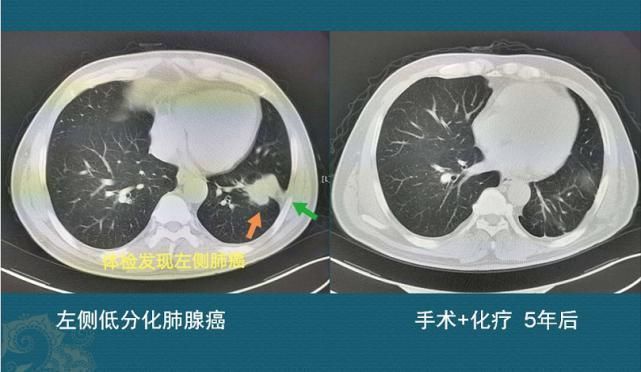

这是一位中年男子,从我们邻市慕名而来,左下肺腺癌接近5厘米,侵犯胸膜,肺门侧淋巴结转移,手术切除配合术后化疗,今年已经第6年了,没有复发!?手术+化疗,治愈了!有手术机会的癌症,都有治愈的希望!